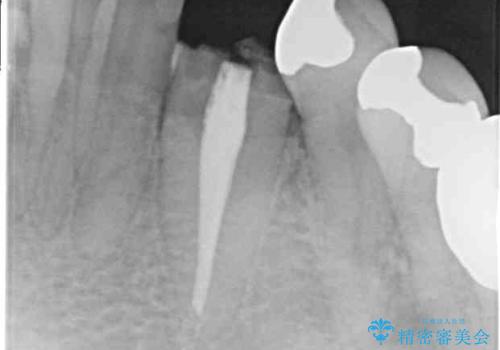

- クラウンがもげてしまった歯が抜歯と言われたとのことで来院された患者様です。

根管治療がされた歯であり、唇側に転位していたため、力がかかったことでクラウンが外れてしまったと判断されました。

麻酔下で歯肉を開いて診察をしたところ、唇側の歯肉縁下に深く歯が欠けている状態でした。

当該歯である犬歯は歯根が長く、安易に抜歯することはおすすめできないため、まずは部分矯正により歯根を引っ張り出し、その後歯周外科処置により歯槽骨や歯肉の状態を整え、最終的にはオールセラミッククラウンにて補綴治療を行うこととしました。